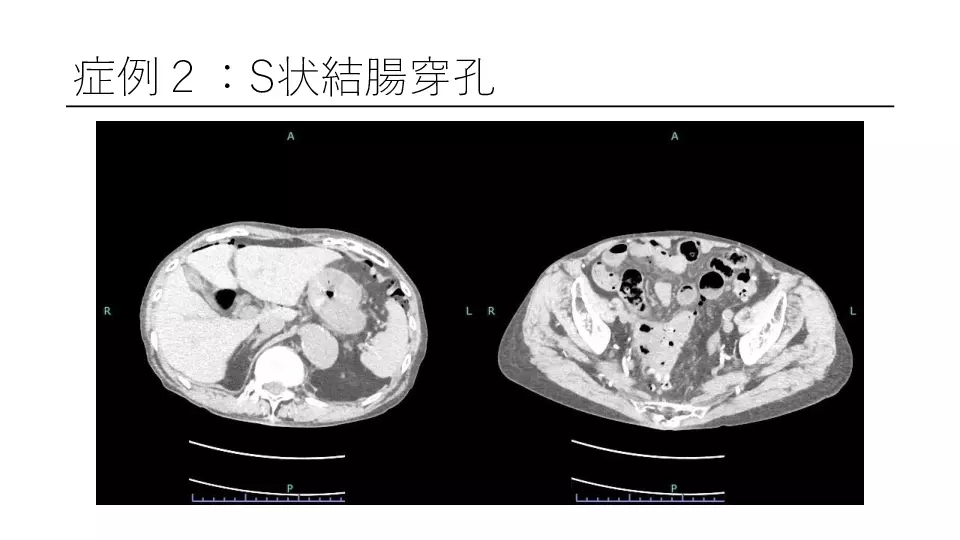

「反跳痛があります」と記載された紹介患者や、研修医からコンサルトにおいて、意外と腹膜炎ではないパターンが散見されます。 若手外科医だからこそ語れる腹膜炎のはなしを聞いてください。 #腹膜炎,#反跳痛の診かた,#コンサルト,